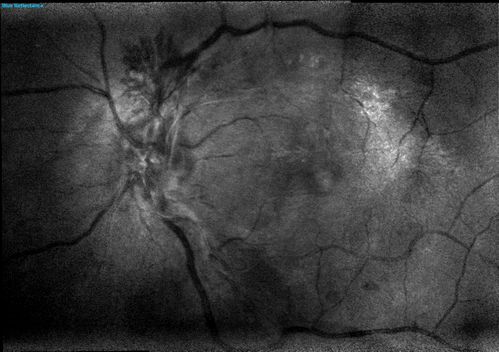

NVD - proliferative diabetic retinopathy Heidelberg False Color

Proliferative Diabetic Retinopathy - Lacy Neovascularization of the Disc - Photo of Fresh Panretinal (Scatter) Photocoagulation